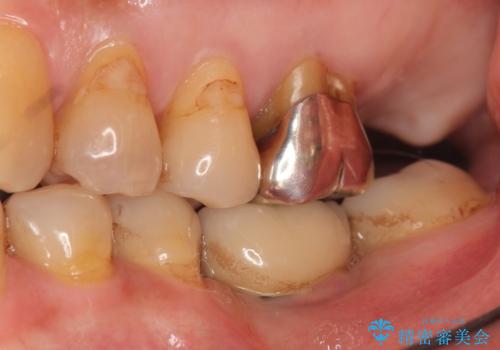

奥歯(左上7)のメタルインレー(銀の詰め物)を除去し精査したところ、奥歯はわれていました。

根尖近くまで深くヒビが入っており保存不可能な状態でした。

患者様のご希望により抜歯してインプラントによる治療を行いました。